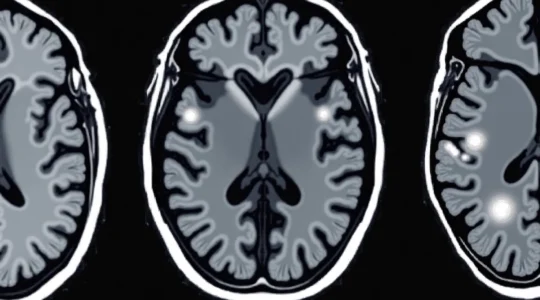

White spots appearing on brain MRI scans represent one of the most frequently encountered radiological findings in modern neuroimaging, yet they can cause considerable anxiety for patients and present diagnostic challenges for clinicians. These hyperintense signals, technically known as white…